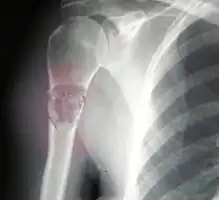

Osteosarcomas tend to occur at the sites of bone growth, presumably because proliferation makes osteoblastic cells in this region prone to acquire mutations that could lead to transformation of cells (the RB gene and p53 gene are commonly involved). Due to this tendency, high incidence of osteosarcoma is seen in some large dog breeds (St. Bernards and Great Danes). The tumor may be localized at the end of the long bone (commonly in the metaphysis). Most often it affects the proximal end of tibia or humerus, or distal end of femur. Osteosarcoma tends to affect regions around the knee in 60% of cases, 15% around the hip, 10% at the shoulder, and 8% in the jaw. The tumor is solid, hard, irregular ("fir-tree," "moth-eaten", or "sun-burst" appearance on X-ray examination) due to the tumor spicules of calcified bone radiating in right angles. These right angles form what is known as a Codman triangle, which is characteristic but not diagnostic of osteosarcoma. Surrounding tissues are infiltrated.

Family physicians and orthopedists rarely see a malignant bone tumor (most bone tumors are benign). The route to osteosarcoma diagnosis usually begins with an X-ray, continues with a combination of scans (CT scan, PET scan, bone scan, MRI) and ends with a surgical biopsy. A characteristic often seen in an X-ray is Codman's triangle, which is basically a subperiosteal lesion formed when the periosteum is raised due to the tumor. Films are suggestive, but bone biopsy is the only definitive method to determine whether a tumor is malignant or benign.

Telangiectactic osteosarcoma of the humerus